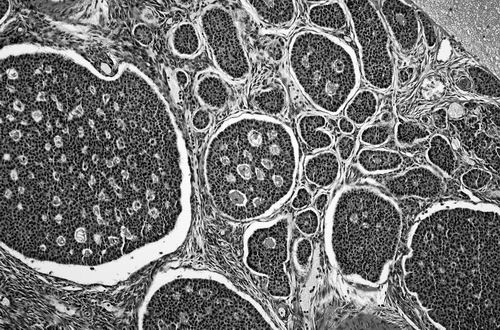

一项临床试验将对卵巢癌细胞进行改造,并将这些细胞重新输给患者。图片来源:PJD/SCIENCE SOURCE

本报讯 在全球部分地区,捐献的血液或血小板等血液成分在输注给患者之前,会用紫外线和核黄素进行消毒。这种名为Mirasol的技术能够消灭多种病毒、细菌和寄生虫。如今,研究人员打算用这种方法对付癌症,即先灭活肿瘤细胞,再将其重新输入患者体内,从而引发有益的免疫反应。他们已在小鼠和狗身上进行了试验,并计划1月在卵巢癌患者中进行第一阶段试验。